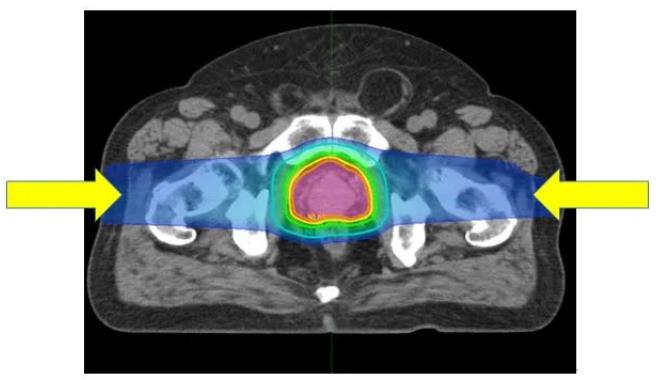

(圖)質子治療前列腺癌:從左右兩個方向進行照射可提供集中在前列腺上的良好劑量分布。